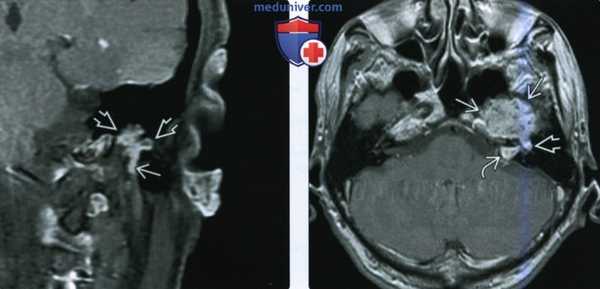

(Слева) На аксиальной КТ с КУ у пациента с нейрофиброматозом 2 типа в передних отделах поверхностной доли околоушной железы визуализируется округлое объемное образование субсантиметрового диапазона. Эта шваннома неравномерно накапливает контраст, кистозные участки в ней отсутствуют из-за малого размера.

(Справа) Накорональной КТ в костном окне определяется равномерное вздутие вертикального сегмента лицевого канала. Шваннома лицевого нерва поднимается через околоушную железу к шилососцевидному отверстию.

(Слева) КТ с КУ, аксиальная проекция, выполненная у пациента с нейрофиброматозом 2 типа. В области переднего края поверхностной доли околоушной железы имеется округлое образование размером менее 1 см. Шваннома неравномерно накапливает контраст, но из-за небольших размеров участки кистозного перерождения отсутствуют.

(Справа) КТ в коаном окне, коронарная проекция. Вертикальный сегмент канала лицевого нерва расширен. Шваннома лицевого нерва из облааи околоушной железы распроараняется в шилососцевидное отвераие.